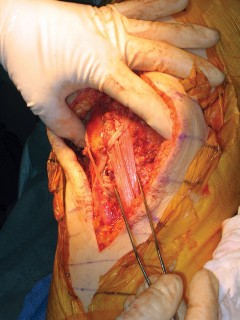

The previous midline longitudinal incision is utilized. Full-thickness fasciocutaneous flaps must be raised to preserve the subdermal vascular plexus. Subcutaneous dissection is strictly avoided to prevent skin flap necrosis. The arthrotomy is typically performed through the previous medial parapatellar approach.

The joint is thoroughly debrided of all fibrotic scar tissue, and the arthroplasty components are inspected. If the components are well-fixed and appropriately positioned, they are retained. The native, dysfunctional patella is typically excised, taking care to preserve the medial and lateral retinacular tissues for later closure and graft coverage. The native quadriceps tendon is identified, mobilized, and prepared to receive the proximal aspect of the reconstruction.